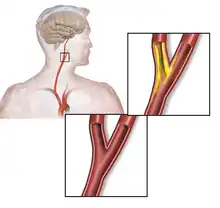

The common carotid artery is the large artery whose pulse can be felt on both sides of the neck under the jaw. On the right side it starts from the brachiocephalic artery (a branch of the aorta), and on the left side the artery comes directly off the aortic arch. At the throat it forks into the internal carotid artery and the external carotid artery. The internal carotid artery supplies the brain, and the external carotid artery supplies the face. This fork is a common site for atherosclerosis, an inflammatory build-up of atheromatous plaque inside the common carotid artery, or the internal carotid arteries that causes them to narrow.[3][4]

Atherosclerosis causes plaque to form within the carotid artery walls, usually at the fork where the common carotid artery divides into the internal and external carotid artery. The plaque build-up can narrow or constrict the artery lumen, a condition called stenosis. Rupture of the plaque can release atherosclerotic debris or blood clots into the artery. A piece of this material can break off and travel (embolize) up through the internal carotid artery into the brain, where it blocks circulation, and can cause death of the brain tissue, a condition referred to as ischemic stroke.[9]

The common carotid artery is the large vertical artery in red. The blood supply to the carotid artery starts at the arch of the aorta (bottom). The carotid artery divides into the internal carotid artery and the external carotid artery. The internal carotid artery supplies the brain. Plaque often builds up at that division and causes a narrowing (stenosis). Pieces of plaque can break off and block the small arteries above in the brain, which causes a stroke. Plaque can also build up at the origin of the carotid artery at the aorta.